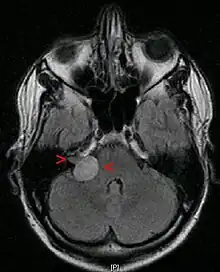

A ressonância magnética é a imagem de escolha, porque pode diferenciar com mais precisão a massa de outros tumores, como meningioma , schwannoma do nervo facial, cisto epidermóide, cisto aracnóide, aneurisma e metástase cerebral. A ressonância magnética também ajuda no planejamento cirúrgico e no acompanhamento do tumor após a cirurgia.[5]